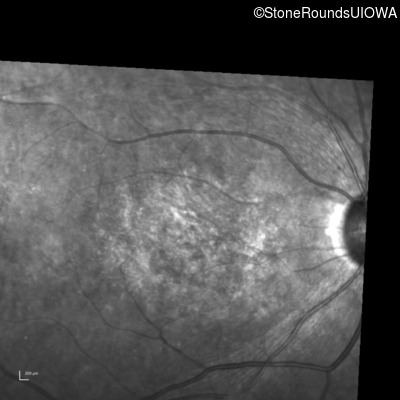

Infrared Fundus Photograph - Right - 20/200 -3

Exemplar

Infrared Fundus Photograph - Left - 20/200 -2